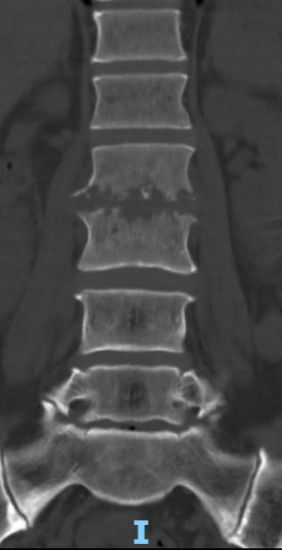

术前腰椎CT

术前腰椎MRI

患者出院后感腰部疼痛持续加重,到色漫网 门诊就诊,以“腰椎感染”收住入院。患者发病后腰椎CT及MRI均提示腰2-3椎间隙变窄,椎板破坏,综合以上资料诊断”腰椎结核”。入院后经口服四联抗结核药物治疗3周,患者自觉腰部疼痛减轻,午后无发热及盗汗后,在全麻下行颈后路病灶清除、椎间植骨、椎弓根钉棒系统内固定术。手术顺利,术后继续抗结核治疗。患者恢复顺利,术后1周下床活动,无特殊不适。术后2周拆线、出院,院外继续口服抗结核药物治疗,定期门诊复查。